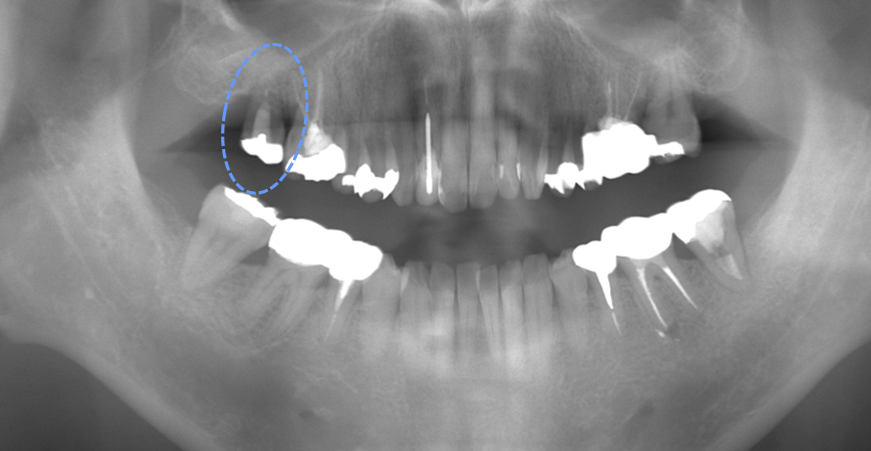

術前のレントゲンです。

パノラマ、デンタルの写真でわかるように大きな病巣です。また、CT撮影も行いました。CT写真の「前から見た断層撮影」では、オレンジ矢印が病巣で、青矢印が下顎管といって神経線維や血管の束が走行している空間です。この下顎管まで病巣が大きくなれば、唇の痺れなど大きな問題が起きることが予想されるため、慎重に根管治療を行う必要がありました。

さらに、デンタルエックス線写真で確認できるように「破折ファイル」といって根管治療中に折れた器具が残っていました。患者さんの症状としては、痛みと歯茎の大きな腫れがありました。

このような大きな病巣がある場合では、きちんと根管治療を行ってからレントゲンにて病巣が縮小してから被せものへと治療を進めていく必要があるのですが、慌てて被せものの治療がなされ当院に来院されました。